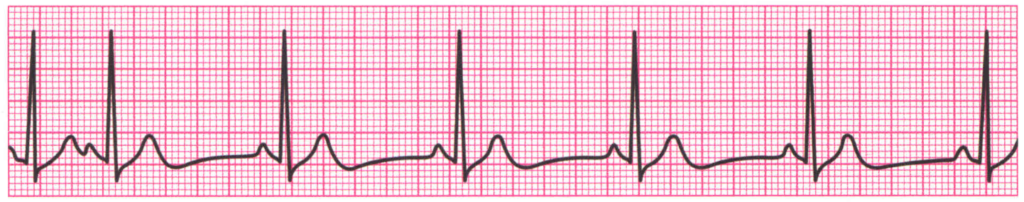

Las contracciones auriculares prematuras (PAC, por sus siglas en inglés) son latidos cardíacos adicionales que se originan en las aurículas en momentos inapropiados. Estas contracciones prematuras tienen características específicas en…

Características de la arritmia sinusal

El nódulo sinoauricular (SA) es considerado el "marcapasos natural" del corazón, ya que es el responsable de iniciar el impulso eléctrico que genera el latido cardíaco. La tasa de descarga…